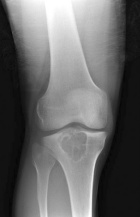

J.O. - 23 year old white male with right knee pain for several years

Zoom image: Radiological image Radiological image.